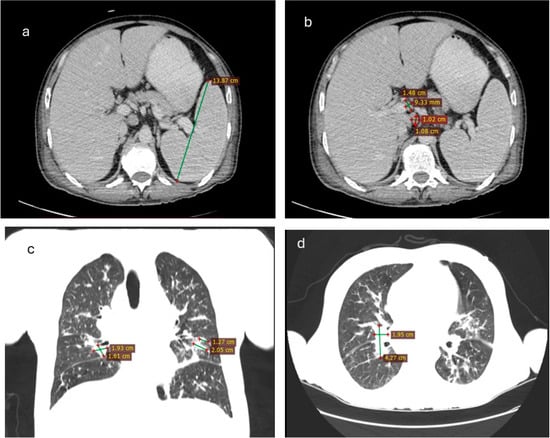

2.4. Diagnostic Investigations